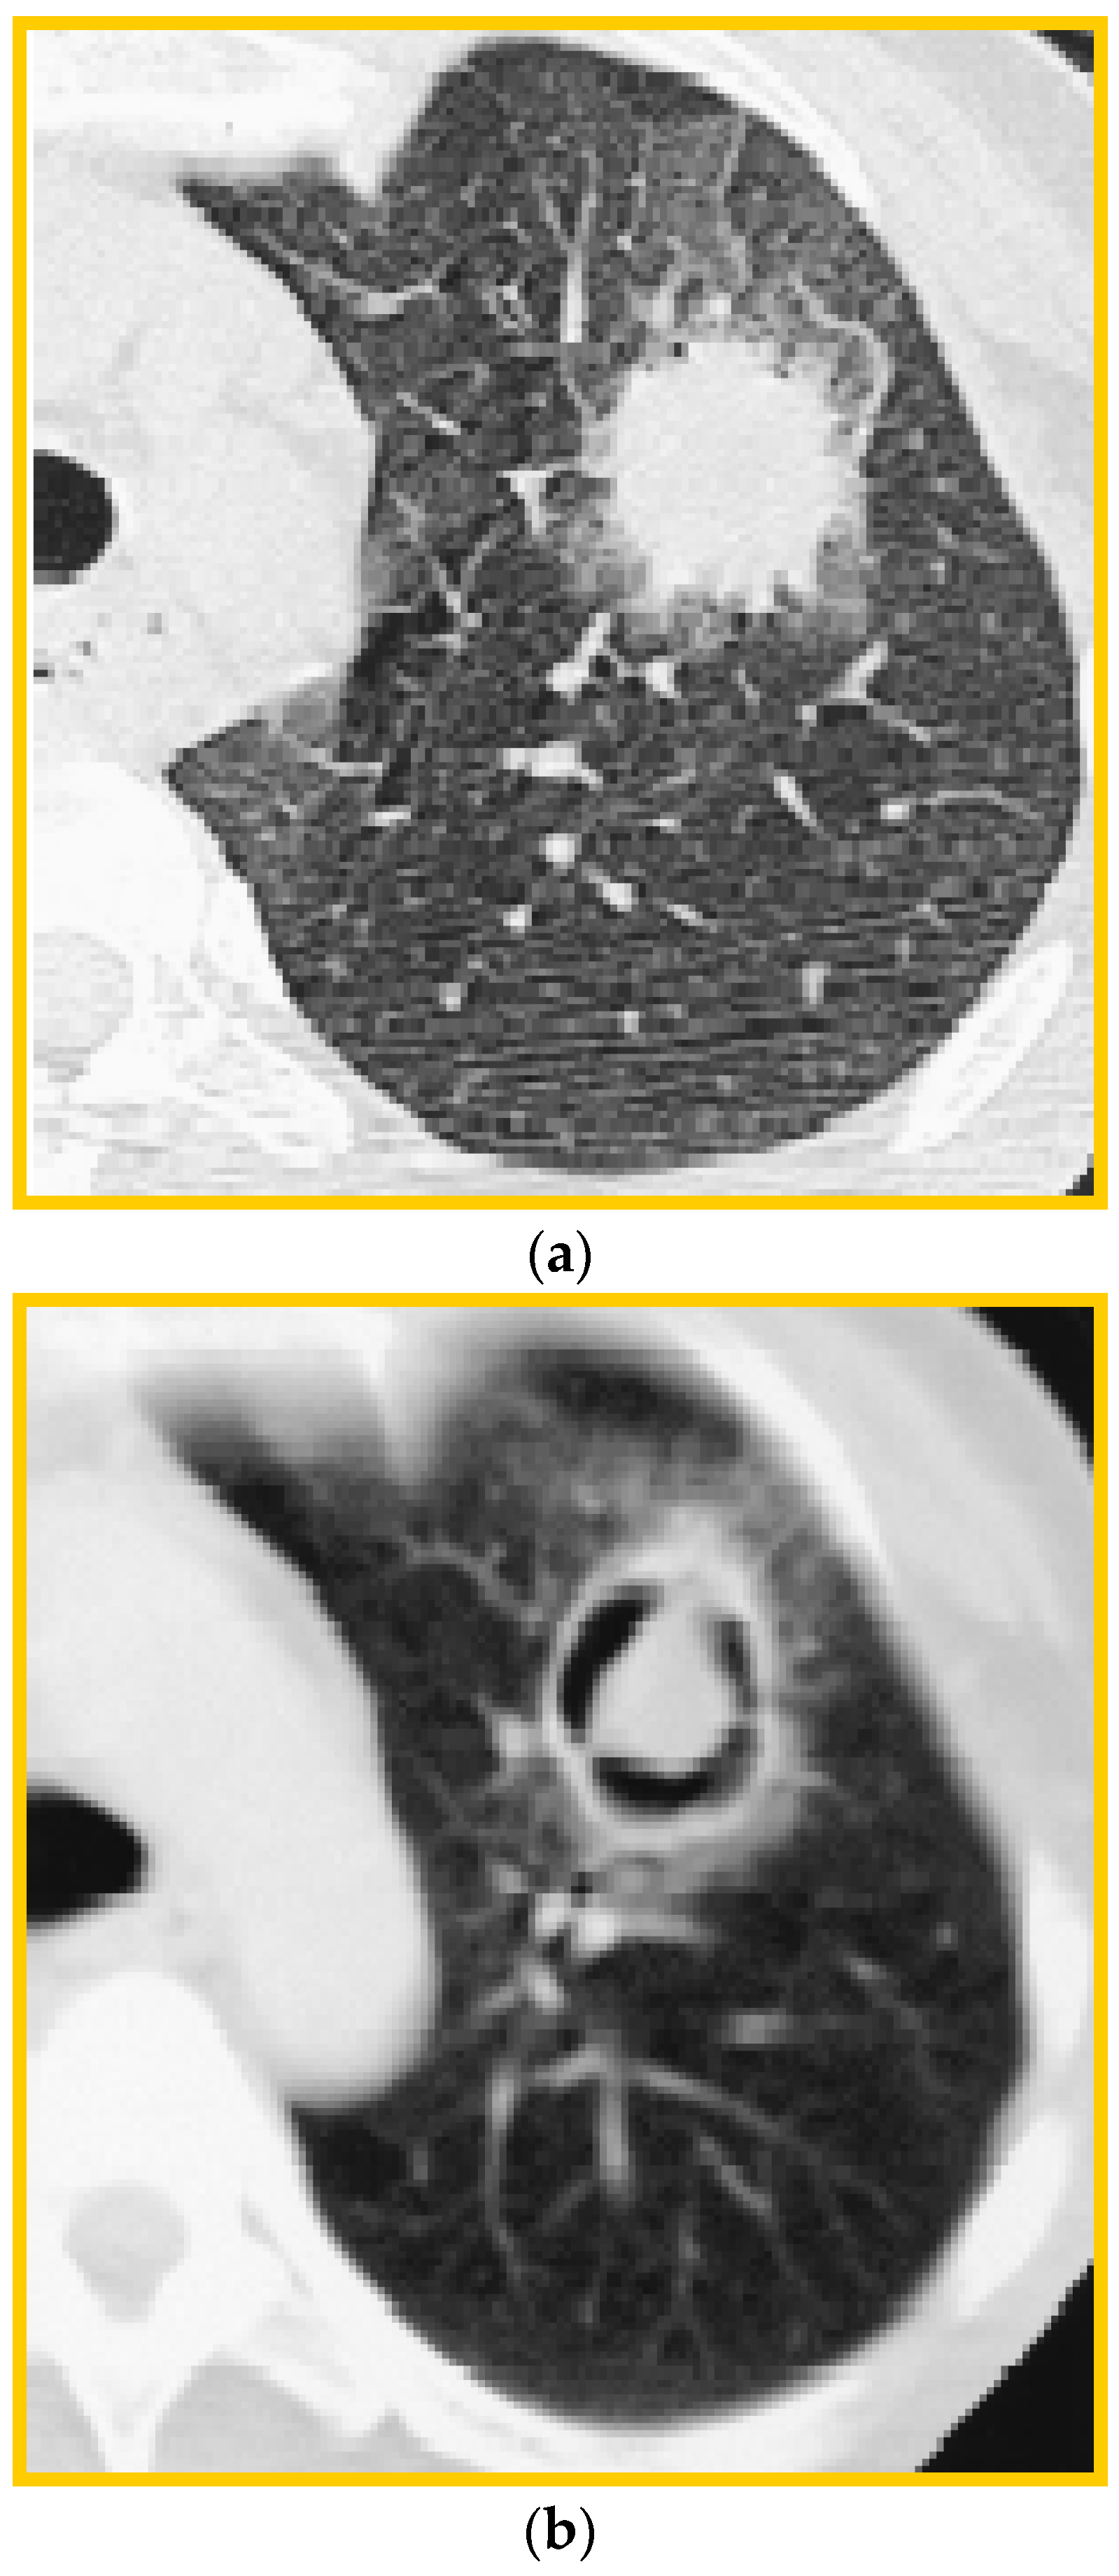

6. Imaging

- Kuhlman, J.E.; Fishman, E.K.; Burch, P.A.; Karp, J.E.; Zerhouni, E.A.; Siegelman, S.S. CT of invasive pulmonary aspergillosis. AJR Am. J. Roentgenol. 1988, 150, 1015–1020. [Google Scholar] [CrossRef] [PubMed]

- Alexander, B.D.; Lamoth, F.; Heussel, C.P.; Prokop, C.S.; Desai, S.R.; Morrissey, C.O.; Baddley, J.W. Guidance on Imaging for Invasive Pulmonary Aspergillosis and Mucormycosis: From the Imaging Working Group for the Revision and Update of the Consensus Definitions of Fungal Disease from the EORTC/MSGERC. Clin. Infect. Dis. 2021, 72 (Suppl. S2), S79–S88. [Google Scholar] [CrossRef] [PubMed]

- Greene, R.E.; Schlamm, H.T.; Oestmann, J.W.; Stark, P.; Durand, C.; Lortholary, O.; Wingard, J.R.; Herbrecht, R.; Ribaud, P.; Patterson, T.F.; et al. Imaging findings in acute invasive pulmonary aspergillosis: Clinical significance of the halo sign. Clin. Infect. Dis. 2007, 44, 373–379. [Google Scholar] [CrossRef] [PubMed]

- Greene, R. The radiological spectrum of pulmonary aspergillosis. Med. Mycol. 2005, 43 (Suppl. S1), S147–S154. [Google Scholar] [CrossRef] [PubMed]

- Desoubeaux, G.; Bailly, É.; Chandenier, J. Diagnosis of invasive pulmonary aspergillosis: Updates and recommendations. Med. Mal. Infect. 2014, 44, 89–101. [Google Scholar] [CrossRef] [PubMed]

- Park, S.Y.; Lim, C.; Lee, S.O.; Choi, S.H.; Kim, Y.S.; Woo, J.H.; Song, J.W.; Kim, M.Y.; Chae, E.J.; Do, K.H.; et al. Computed tomography findings in invasive pulmonary aspergillosis in non-neutropenic transplant recipients and neutropenic patients, and their prognostic value. J. Infect. 2011, 63, 447–456. [Google Scholar] [CrossRef] [PubMed]